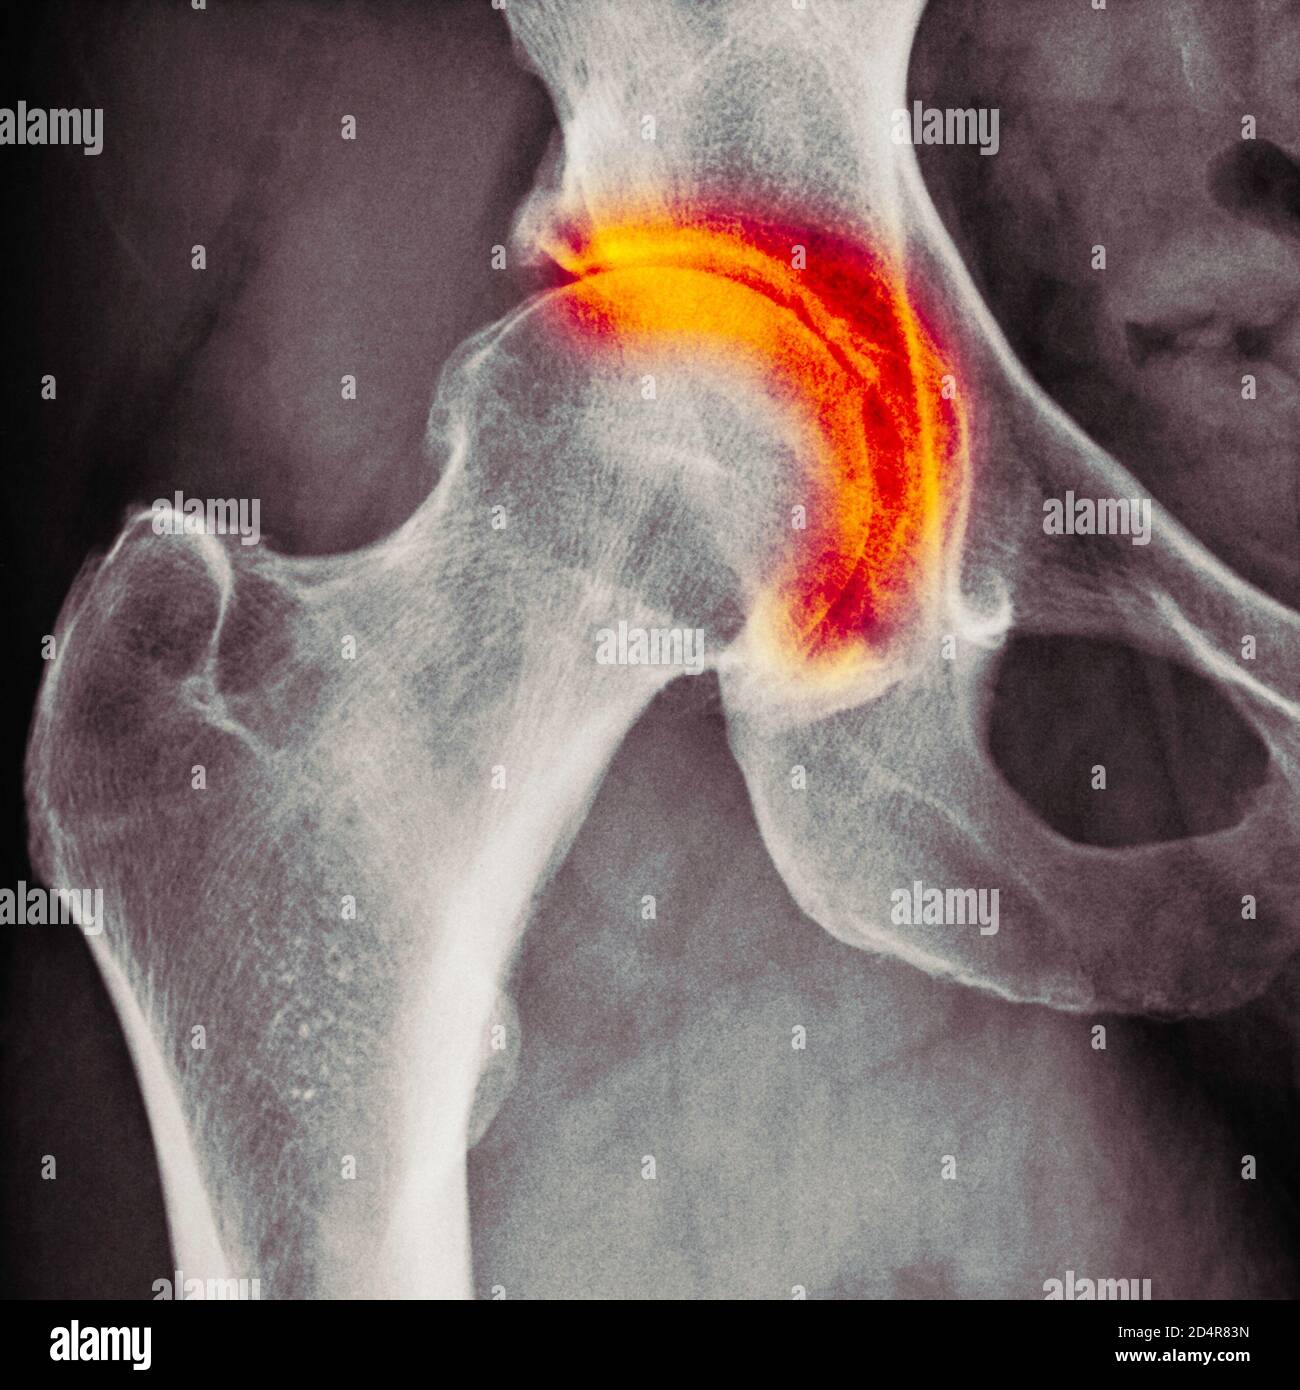

Endstage degenerative arthritis of the hip Image Hip X Ray Arthritis Osteoarthritis of the hip can range in severity; Diagnosis can be made with. Osteoarthritis of the hip can be graded according to its severity. Learn how to assess a person with suspected osteoarthritis (oa) and exclude alternative or additional diagnoses. Learn how doctors diagnose and treat this condition with. Hip osteoarthritis is degenerative disease of the hip joint that causes. Hip X Ray Arthritis.

Osteoarthritis of the hip, Xray Stock Image C040/3326 Science Hip X Ray Arthritis Learn how to assess a person with suspected osteoarthritis (oa) and exclude alternative or additional diagnoses. Osteoarthritis of the hip can range in severity; Hip osteoarthritis is degenerative disease of the hip joint that causes progressive loss of articular cartilage of the femoral head and acetabulum. Osteoarthritis of the hip can be graded according to its severity. Learn how doctors. Hip X Ray Arthritis.

Arthritis of the hip, Xray Stock Photo Alamy Hip X Ray Arthritis Osteoarthritis of the hip can be graded according to its severity. Diagnosis can be made with. Hip osteoarthritis is degenerative disease of the hip joint that causes progressive loss of articular cartilage of the femoral head and acetabulum. Learn how to assess a person with suspected osteoarthritis (oa) and exclude alternative or additional diagnoses. Learn how doctors diagnose and treat. Hip X Ray Arthritis.